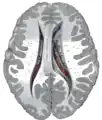

Ventricles of brain and basal ganglia. Superior view, horizontal section, deep dissection

The caudate nuclei are located near the center of the brain, sitting astride the thalamus. There is a caudate nucleus within each hemisphere of the brain. Individually, they resemble a C-shape structure with a wider "head" (caput in Latin) at the front, tapering to a "body" (corpus) and a "tail" (cauda). Sometimes a part of the caudate nucleus is referred to as the "knee" (genu).[7] The caudate head receives its blood supply from the lenticulostriate artery while the tail of the caudate receives its blood supply from the anterior choroidal artery.[8]

The head and body of the caudate nucleus form part of the floor of the anterior horn of the lateral ventricle. After the body travels briefly towards the back of the head, the tail curves back toward the anterior, forming the roof of the inferior horn of the lateral ventricle. This means that a coronal (on a plane parallel to the face) section that cuts through the tail will also cross the body and head of the caudate nucleus.